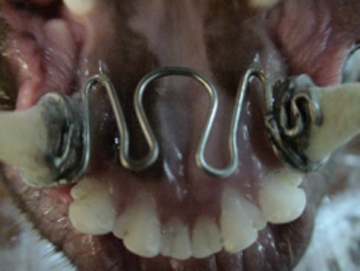

La persistencia de los caninos deciduos provocan interferencias oclusales severas por la erupción ectópica de los caninos permanentes que al no tener una guía adecuada de erupción, tienden a colocarse mesialmente a su posición normal. Esta situación provoca que en vez de que la superficie mesial de los caninos superiores permanentes contacte con la superficie distal de los caninos inferiores, sea la punta incisiva de los caninos superiores la que contacta con la superficie distal de los caninos inferiores provocando un adelantamiento de la mandíbula presentándose una pseudo oclusión clase III, o sea un pseudo prognatismo con mordida cruzada anterior. Por eso, es importante antes de que erupcionen los caninos permanentes saber cuando es el periodo de exfoliación de los caninos temporales para en caso de ser necesario extraerlos y evitar esta grave maloclusión. Otra situación no tan común es cuando existen dientes supernumerarios que provocan apiñamiento. En estos casos se extraen los dientes supernumerarios antes de que se presente el apiñamiento severo y de esta manera evitamos la maloclusión.